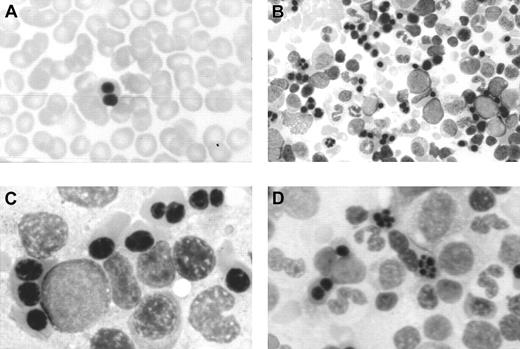

In this period, an extensive study ruled out red cell enzyme, membrane, hemoglobin, and thalassemic diseases. Tests for maternofetal isoimmunization were normal, and a bone marrow biopsy showed a normal osteogenesis with erythroid hyperplasia, excluding an aplastic red cell anemia. His red cells showed a normal agglutinability with anti-i antibody, and an acidified serum lysis test was negative (HEMPAS negative) in 3 samples and against 25 sera. At 3 months of life when the immunohematologic study was carried out, his hemoglobin was 67 g/L, mean corpuscular volume was 80 fL, platelets were 568 × 109/L, leucocytes were 10.2 × 109/L, including 10% of nucleated red cells, and reticulocytes were 0.5% (0.013 × 1012/L). Red cell morphology in peripheral blood showed scant binuclear erythroblasts (2%) (Figure 1).

Optical microscopy morphology of peripheral and bone marrow hematopoiesis.

Binucleate erythroblast in peripheral blood (A). Erythroid hyperplasia with marked abnormalities (binucleate, trinucleate, and multinucleate late erythroblasts) (B,C,D). Abnormal erythroblasts showing anomalous distribution of chromatin (C,D), binucleate erythroblasts, and isolated trinuclear, tetranuclear (B), and aberrant multinuclear erythroblasts (B,D). May-Grünwald-Giemsa stain. Original magnifications: A and D, × 400; B, × 200; C, × 1000.

Optical microscopy morphology of peripheral and bone marrow hematopoiesis.

Binucleate erythroblast in peripheral blood (A). Erythroid hyperplasia with marked abnormalities (binucleate, trinucleate, and multinucleate late erythroblasts) (B,C,D). Abnormal erythroblasts showing anomalous distribution of chromatin (C,D), binucleate erythroblasts, and isolated trinuclear, tetranuclear (B), and aberrant multinuclear erythroblasts (B,D). May-Grünwald-Giemsa stain. Original magnifications: A and D, × 400; B, × 200; C, × 1000.

At the age of 2 months a bone marrow examination showed erythroid hyperplasia and markedly abnormal erythropoiesis (Figure 1), including a substantial proportion of binuclear erythroblasts (20%) and a much smaller proportion of trinuclear, tetranuclear, and multinuclear erythroblasts (2%). Sideroblastic or megaloblastic anemias were ruled out. Granulocytopoiesis and megakariocytopoiesis were normal.